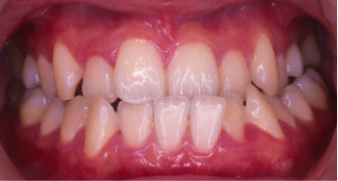

過蓋咬合(かがいこうごう)※ 非抜歯

20歳/女性

悩み:噛み合わせが深い

下の前歯が上の歯茎に食い込んでいる状態

治療期間:約2年

治療前

深い噛み合せを改善する治療が必要になりました。

先に深い噛み合せを上げないと矯正装置がつかないので、噛み合せの深さを改善する治療から行なう矯正治療となりました。